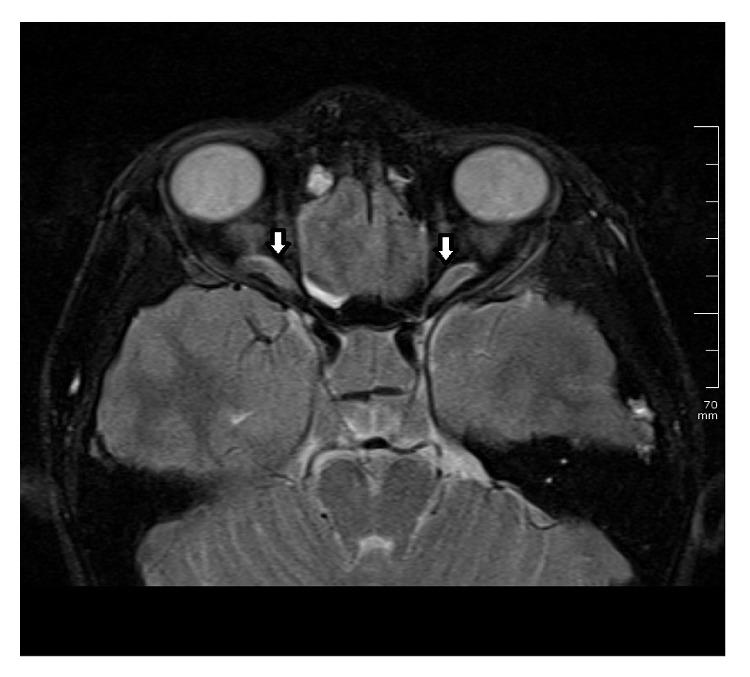

Objective. Meningiomas are benign primary meningeal tumors and are seen rare in children and adolescents. Clinical Presentation and Intervention. A 15-year-old Turkish boy reported a 1-month history of headache and blurred vision in both eyes. His visual acuity was 0.3 in both eyes with papilledema. Magnetic resonance imaging showed a 77 × 97 × 77 mm intracranial-extra-axial frontal lesion which compresses the chiasm. He was diagnosed with intracranial meningioma and referred to neurosurgery clinic. Conclusion. Ophthalmologists should be aware of the fact that papilledema and low vision can be caused by an intracranial tumor which compresses optic chiasm.

目的。脑膜瘤是原发性良性脑膜肿瘤,在儿童和青少年中罕见。临床表现与干预。一名15岁的土耳其男孩报告有1个月的头痛和双眼视力模糊病史。他双眼视力均为0.3,伴有视乳头水肿。磁共振成像显示一个77×97×77毫米的颅内-轴外额叶病变,压迫视交叉。他被诊断为颅内脑膜瘤,并被转诊至神经外科诊所。结论。眼科医生应意识到视乳头水肿和视力低下可能由压迫视交叉的颅内肿瘤引起。